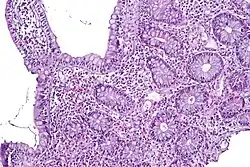

Under light microscopy, C. jejuni has a characteristic "sea-gull" shape as a consequence of its helical form. Campylobacter is grown on specially selective "CAMP" agar plates at 42 °C, the normal avian body temperature, rather than at 37 °C, the temperature at which most other pathogenic bacteria are grown. Since the colonies are oxidase positive, they usually only grow in scanty amounts on the plates. Microaerophilic conditions are required for luxurious growth. A selective blood agar medium (Skirrow's medium) can be used. Greater selectivity can be gained with an infusion of a cocktail of antibiotics: vancomycin, polymixin-B, trimethoprim, and actidione (Preston's agar),[63] and growth under microaerophilic conditions at 42 °C.